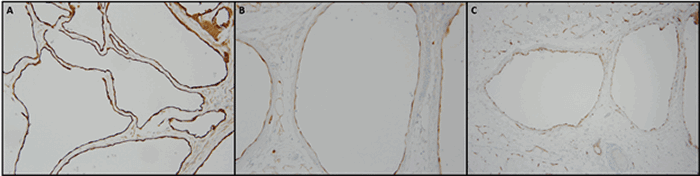

At this time, the patient was referred to our general surgery clinic for evaluation. Given the increasing size of the lesion and worsening abdominal pain, the decision was made to proceed with an exploratory laparotomy. An effort was made to resect the visible lesion and avoid the rupture or spillage of cystic content. A pink-tan, smooth, intact, thin-walled cystic mass (Figure 2) was removed. The mass weighed 136 grams, measured 9.5 cm × 8.1 cm × 4.0 cm, and had multiple attached daughter cysts (0.2 cm‒0.7 cm). All cysts contained a thin, clear fluid with no solid areas identified. The histologic examination was consistent with BMPM, showing cysts lined with mesothelial cells and foci of fibroblastic/mesothelial proliferation along with numerous blood vessels within the stroma (Figure 3).

Figure 3. Histologic Images. Published with Permission

A) Demonstrates AE 1-3 staining at 200x magnification; B) Demonstrates calretinin staining at 200x magnification; C) Demonstrates WT1 staining at 100x magnification

Definitive diagnosis of BMPM is made via evaluation of cyst aspirate and histological examination of cyst walls. BMPM is composed of thin-walled cysts lined by single-layered mesothelial cells without atypia and filled with serous fluid. Confirmatory testing can be achieved with positive immunohistochemical staining of mesothelial cells for calretinin and WT1.10,12